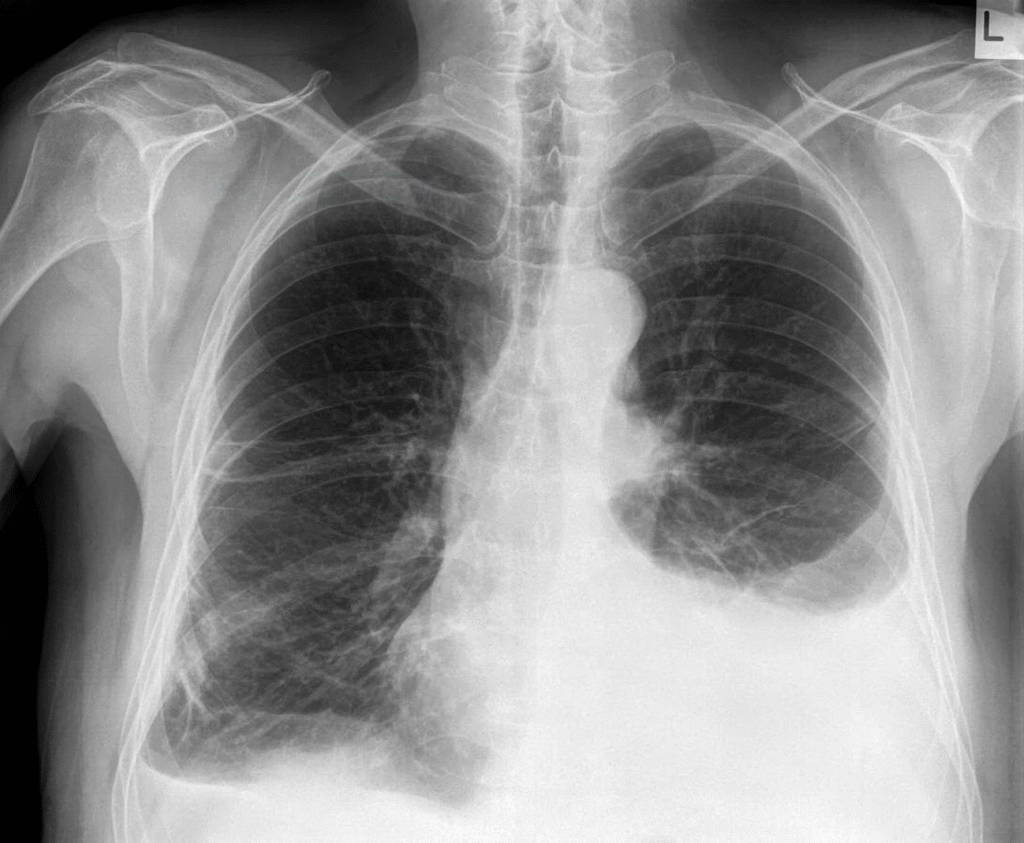

Bildgebung:

- Rö-Thorax: Verschattung basal, Spiegelbildung (Seitenlageaufnahme)